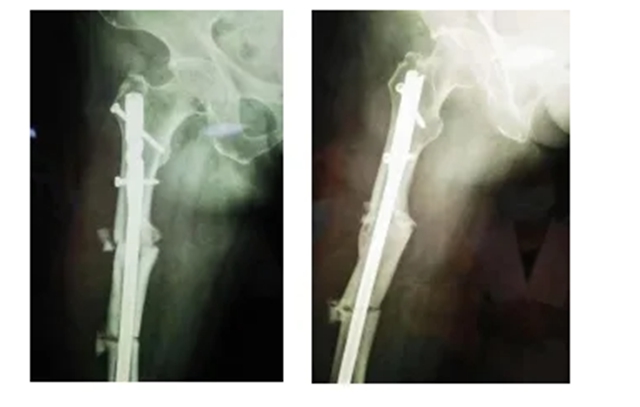

据汪永泉主任介绍,此次手术很成功,术后通过观察,病人目前没有血管的危象,而且整个神经没有牵拉,而且病人整个下肢体长度,也基本达到术前预想的恢复长度。

术后拍摄的X光片

但因张女士属于股骨上段骨折畸形以后手术归正,整个股骨头的负重区已经发生了一些改变,髋关节关节炎也可能存在,因此张女士还需进行后续的康复性治疗和护理。